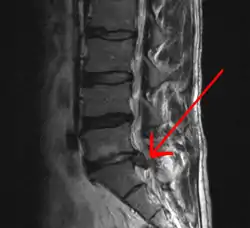

A herniated disc as seen on MRI, one possible cause of low back pain

The straight leg raise test can detect pain originating from a herniated disc. When warranted, imaging such as MRI can provide clear detail about disc related causes of back pain (L4–L5 disc herniation shown)